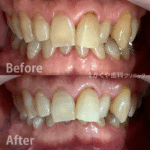

ホワイトニング治療例(60代 男性)_0003

ホワイトニング前後の比較